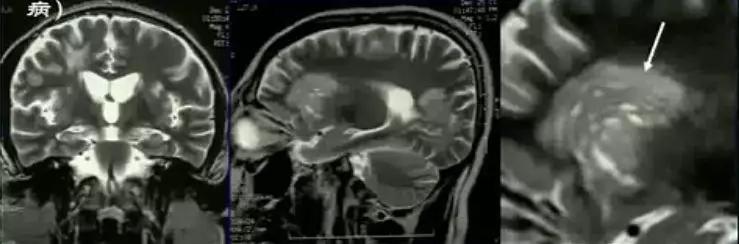

DPT 多为单发,偶为多发。发病部位为中枢神经系统任何部位,主要累及皮层下白质。表现为局灶性肿块,形态欠规则,边界不清,周围水肿明显,占位效应明显。病灶信号多较均匀,在 T1WI 上呈不均匀稍低信号,T2WI 上呈高信号,在 DWI 上可呈略低、等或略高信号,少数可合并囊变或出血,上述平扫 MRI 表现与脑内原发性及转移性肿瘤特别是脑胶质细胞肿瘤难以鉴别,容易误诊。在 MRI 增强扫描上,由于 DPT 病灶常破坏血-脑脊液屏障,病灶可出现不同程度强化,其强化表现具有特征性,病灶可呈环形、斑片形、团块形等多种强化方式。其中,最重要的影像学特征为「开环征」与「垂直征」。

由于 DPT 的 MRI 表现与胶质瘤及转移瘤有很多相似之处,因此,常常发生误诊。增强扫描对于 DPT 与脑肿瘤鉴别有一定价值,DPT 的特征性表现为「开环征」和「垂直征」,尤其是垂直征,对于 DPT 具有很高的提示价值。DPT 主要应与胶质瘤鉴别。低级别胶质瘤强化不明显,高级别胶质瘤强化明显,有明显的坏死、水肿及占位效应,而脱髓鞘性假瘤为开环样强化、轻到中度水肿,且 DPT 水肿有随病程进展而消退的特点。